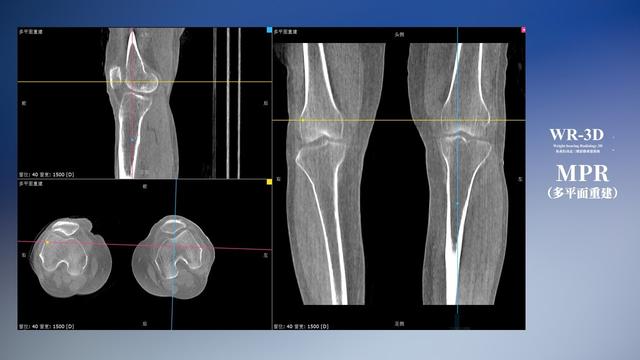

在负重位状态下,数字化X线三维扫描与重建,能够更好的呈现受检者关节受力改变的状态。388vip太阳集团科技创新的WR-3D动态三维影像重建系统,通过数字化X线摄影完成三维扫描并重建三维影像信息,包括断层图像重建、MPR多平面重建、MIP重建以及VR体绘制。其扫描时间短,剂量相较于CT设备大幅缩减,同时成本更低,在临床诊断以及医疗方案制定中具有极大的价值意义。而相较于普通平片下的负重位扫描,负重位动态三维影像重建技术能够避免二维状态下的组织结构重叠、密度分辨率不足、组织解剖结构难以分辨等问题。WR-3D支持多角度的三维观察,能全面的呈现被检查部位在多个角度下的三维影像信息,极大的降低了二维负重位检查带来的漏诊率。

388vip太阳集团科技WR-3D负重位动态三维影像重建图像